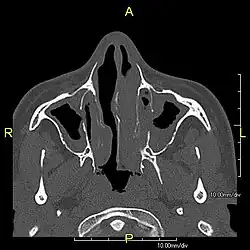

| Complications | Chronic recurrent respiratory infections, including sinusitis, bronchitis, pneumonia, and otitis media.[2] |

Around 80% of people with primary ciliary dyskinesia experience respiratory problems beginning within a day of birth. Many have a collapsed lobe of the lung and blood oxygen low enough to require treatment with supplemental oxygen.[1] Within the first few months of life, most develop a chronic mucus-producing cough and runny nose.[1] The main consequence of impaired ciliary function is reduced or absent mucus clearance from the lungs, and susceptibility to chronic recurrent respiratory infections, including sinusitis, bronchitis, pneumonia, and otitis media. Progressive damage to the respiratory system is common, including progressive bronchiectasis beginning in early childhood, and sinus disease (sometimes becoming severe in adults). However, diagnosis is often missed early in life despite the characteristic signs and symptoms.[2] In males, immotility of sperm can lead to infertility, although conception remains possible through the use of in vitro fertilization, there also are reported cases where sperm were able to move.[8] Trials have also shown that there is a marked reduction in fertility in females with Kartagener's syndrome due to dysfunction of the oviductal cilia.[9]

Many affected individuals experience hearing loss and show symptoms of otitis media which demonstrates variable responsiveness to the insertion of myringotomy tubes or grommets. Some patients have a poor sense of smell, which is believed to accompany high mucus production in the sinuses (although others report normal – or even acute – sensitivity to smell and taste). Clinical progression of the disease is variable, with lung transplantation required in severe cases. Susceptibility to infections can be drastically reduced by an early diagnosis. Treatment with various chest physiotherapy techniques has been observed to reduce the incidence of lung infection and to slow the progression of bronchiectasis dramatically. Aggressive treatment of sinus disease beginning at an early age is believed to slow long-term sinus damage (although this has not yet been adequately documented). Aggressive measures to enhance clearance of mucus, prevent respiratory infections, and treat bacterial superinfections have been observed to slow lung-disease progression. The predicted incidence is 1 in approximately 7500.[10]

Diagnosis

Several diagnostic tests for this condition have been proposed.[5] These include nasal nitric oxide levels as a screening test, light microscopy of biopsies for ciliary beat pattern and frequency and electron microscopic examination of dynein arms, as the definite diagnosis method. Genetic testing has also been proposed but this is difficult given that there are multiple genes involved.[6]